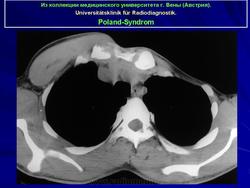

Синдром Поланда (СП) представляет собой комплекс пороков, включающий отсутствие большой и малой грудной мышц, синдактилию, брахидактилию, ателию (отсутствие соска молочной железы) и/или амастию (отсутствие самой молочной железы), деформацию или отсутствие нескольких ребер, отсутствие волос в подмышечной впадине и снижение толщины подкожно-жирового слоя. Отдельные компоненты этого синдрома впервые были описаны Lallemand LM (1826) и Frorier R (1839). Однако назван он по имени английского студента-медика Alfred Poland, который в 1841 году опубликовал частичное описание данной деформации. Полную характеристику синдрома в литературе впервые опубликовал Thompson J в 1895 году.

Поланда синдром (Poland syndrome)